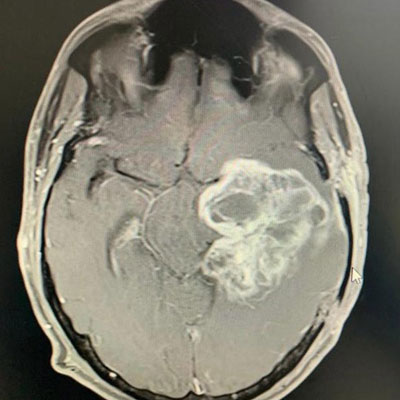

Dr. Ujwal Yeole is an experienced neurosurgeon specializes in treating a wide spectrum of neurological conditions including neuro-oncology, peripheral nerve disorders, vascular disorders, spinal pathologies, pediatric neurosurgery, neuro-trauma and skull base neuroendoscopic procedures.